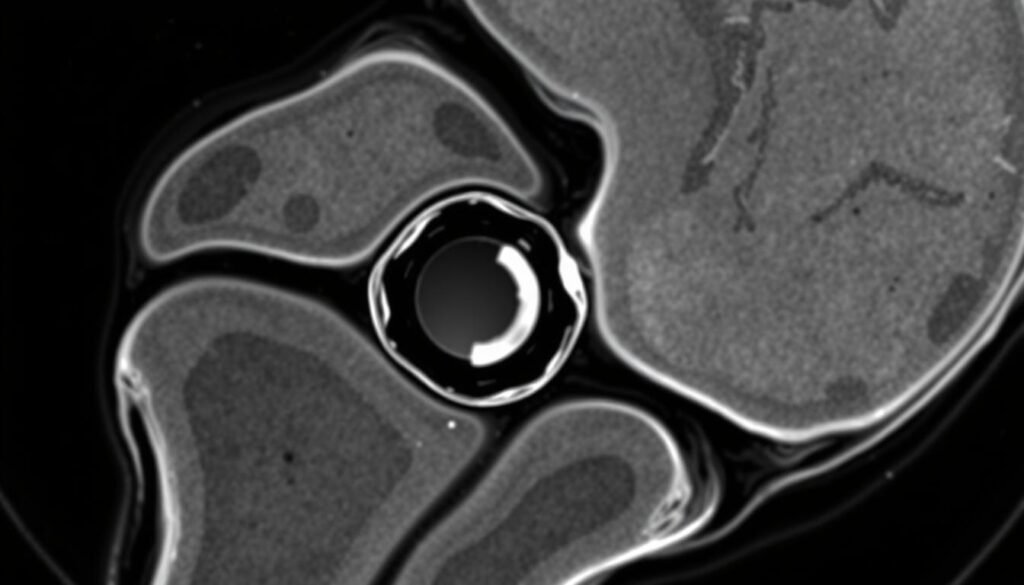

Bildgebende Verfahren

Zur Bestätigung der Diagnose und genauen Beurteilung des Meniskusrisses werden verschiedene bildgebende Verfahren eingesetzt:

Magnetresonanztomographie (MRT)

Die wichtigste Untersuchung bei Verdacht auf Meniskusriss. Zeigt detailliert Weichteilstrukturen und kann Art, Lage und Ausmaß des Risses genau darstellen.

Arthroskopie

Gleichzeitig diagnostisches und therapeutisches Verfahren. Eine kleine Kamera wird ins Kniegelenk eingeführt, um den Meniskus direkt zu beurteilen und ggf. zu behandeln.

Die Magnetresonanztomographie (MRT) ist das wichtigste bildgebende Verfahren zur Diagnose von Meniskus Verletzungen.